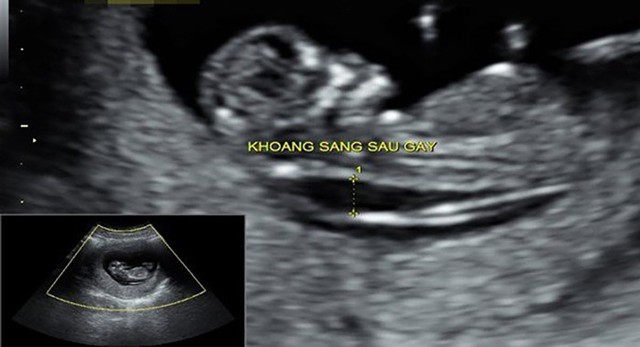

Kết quả đo độ mờ da gáy cao nhưng chọc ối bình thường có thể xảy ra trong một số trường hợp. Việc đo độ mờ da gáy chỉ cung cấp thông tin một phần, và đôi khi nó có thể không phản ánh đúng tình hình của thai nhi. Trong trường hợp này, bác sĩ sẽ tiếp tục theo dõi và đánh giá sự phát triển của thai nhi bằng cách sử dụng kết quả chọc ối để đưa ra đánh giá tổng quan về tình hình sức khỏe của thai nhi. Hãy cùng Nhà thuốc Long Châu tìm hiểu về trường hợp này nhé!

Siêu âm đo độ mờ da gáy là một trong các phương pháp xác định nguy cơ mắc dị tật ở thai nhi mà mẹ cần làm. Vậy siêu âm 2D có đo được độ mờ da gáy không? Vấn đề đó sẽ được giải đáp qua bài viết sau đây.

Đo độ mờ da gáy là một trong những bước quan trọng nhằm xác định nguy cơ bị bệnh Down ở trẻ nhỏ. Vậy nguyên nhân độ mờ da gáy cao ở bé là gì? Hãy cùng chúng tôi tìm hiểu lý do đó qua bài viết sau đây nhé.